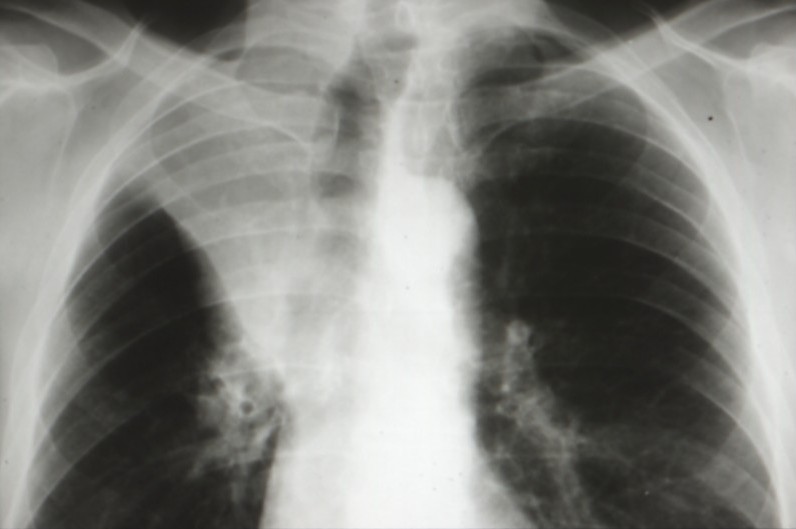

Cancers bronchiques